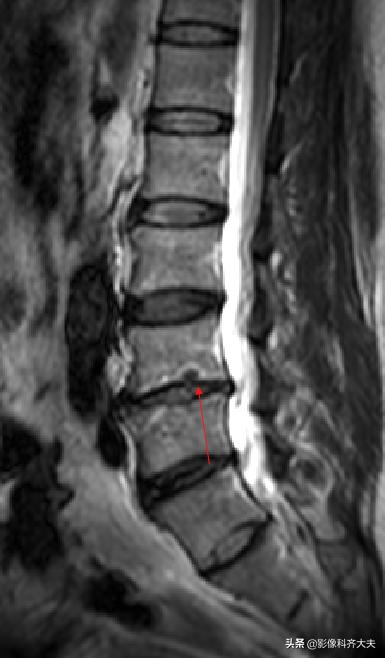

MRI:腰椎间盘突出

MRI:腰 5-骶1间盘脱出

MRI:腰椎间盘脱出

MRI:髓核游离